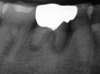

- Cas clinique 2 :

La racine de la première molaire est courte et fracturée. L’os alvéolaire est infecté également ici depuis longtemps et contre-indique également une extraction-implantation immédiate.

L’alvéole est comblée et des sutures viennent plaquer une éponge pour rendre étanche le comblement osseux.